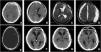

A 40-year-old Caucasian male suffered a traumatic brain injury that required a decompressive craniectomy. One month after initial trauma autologous cranioplasty was performed. A ventriculoperitoneal shunt was also placed. Neurological status progressively improved but his therapist noted cognitive status decline 8 months later. Follow-up computed tomography showed a progressive sinking bone flap. The patient underwent bone flap removal and a custom-made calcium phosphate-based implant was inserted, leading to symptoms resolution.

Bone resorption has been described as the main cause of sinking bone flap following cranioplasty. This entity may manifest with symptoms of overdrainage in patients with cerebrospinal fluid shunt devices.